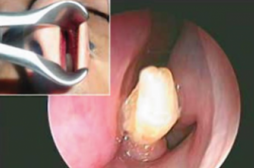

névralgie d'Arnold